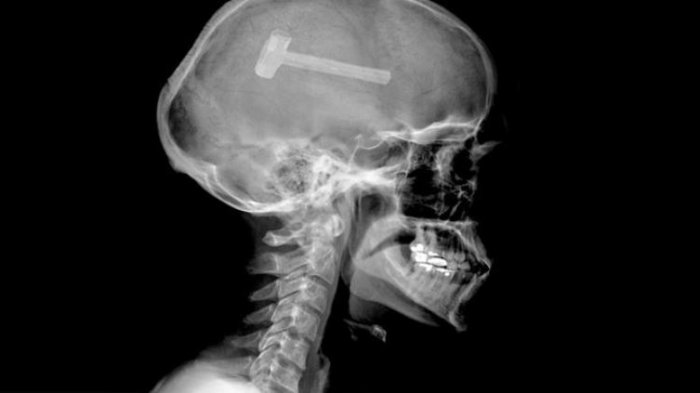

2. Paku

Dante Autello tak pernah sadar jika ada paku yang tertancap di kepalanya.

Kejadian itu terjadi saat dirinya berniat untuk memaku menggunakan alat paku berbentuk pistol.

Sayang saat menggunakannya dia tergelincir dan mengenai kepalanya.

Tanpa sadar ada paku yang menancap di kepalanya.

Sampai 48 jam kemudian saat kembali, sang istri melihat kepala suaminya ini dan mengetahui ada paku yang tertancap.